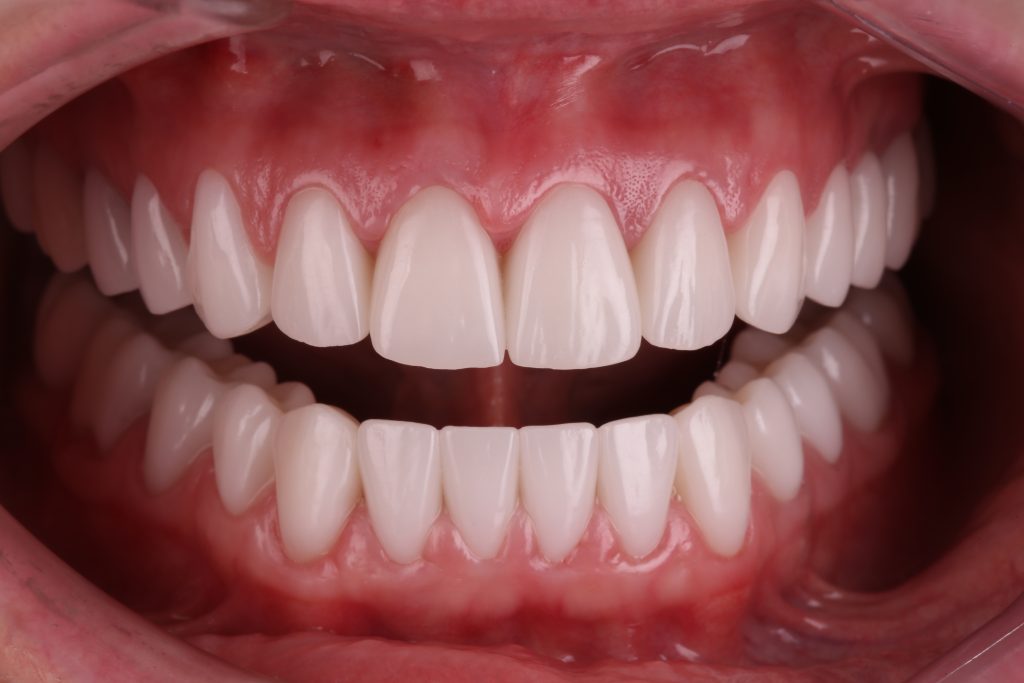

Итоговый результат комплексной ортопедической реабилитации вместе с Diagnocat AI

Через 18 месяцев от начала лечения выполнена повторная КЛКТ с анализом данных системой Diagnocat